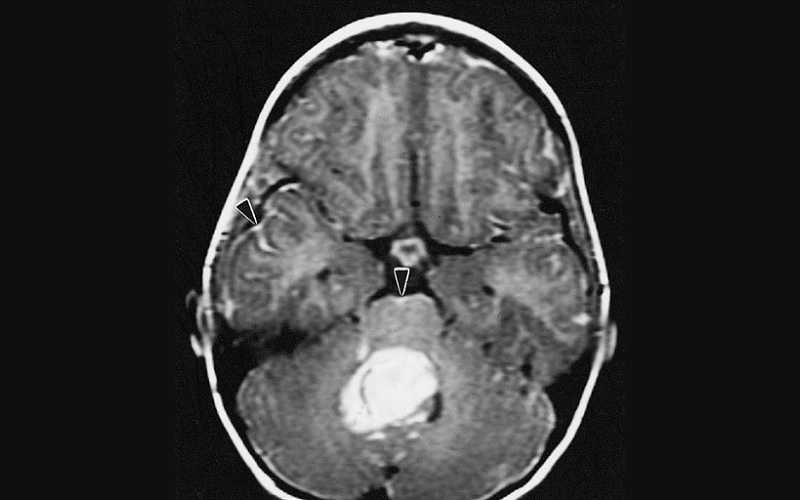

Onderzoekers uit Duitsland en Denemarken evalueerden monsters van hersenweefsel van zowel muismodellen als post-mortem mensen, op zoek naar de aanwezigheid en distributie van SARS-CoV-2 spike-eiwit. Zij keken specifiek naar de schedel-meninges-hersenas.

Zij ontdekten dat spike-eiwit van de injecties zich ophoopt in het schedelmerg, de hersenvliezen en het hersenparenchym, en legden verder uit dat de “injectie van het spike-eiwit alleen al celdood in de hersenen veroorzaakte, wat wijst op een direct effect op het hersenweefsel.”

Zelfs lang nadat een “positieve” covid-test en infectie is verstreken, blijven de spike-eiwitten in de menselijke hersenen achter. Onderzoekers zeggen dat deze blijvende spike-eiwitten kunnen bijdragen aan neurologische symptomen op lange termijn, zoals “hersenmist” en verlies van hersenweefsel.

Moreover, spike S1 was also detected in the brain prefrontal cortex.